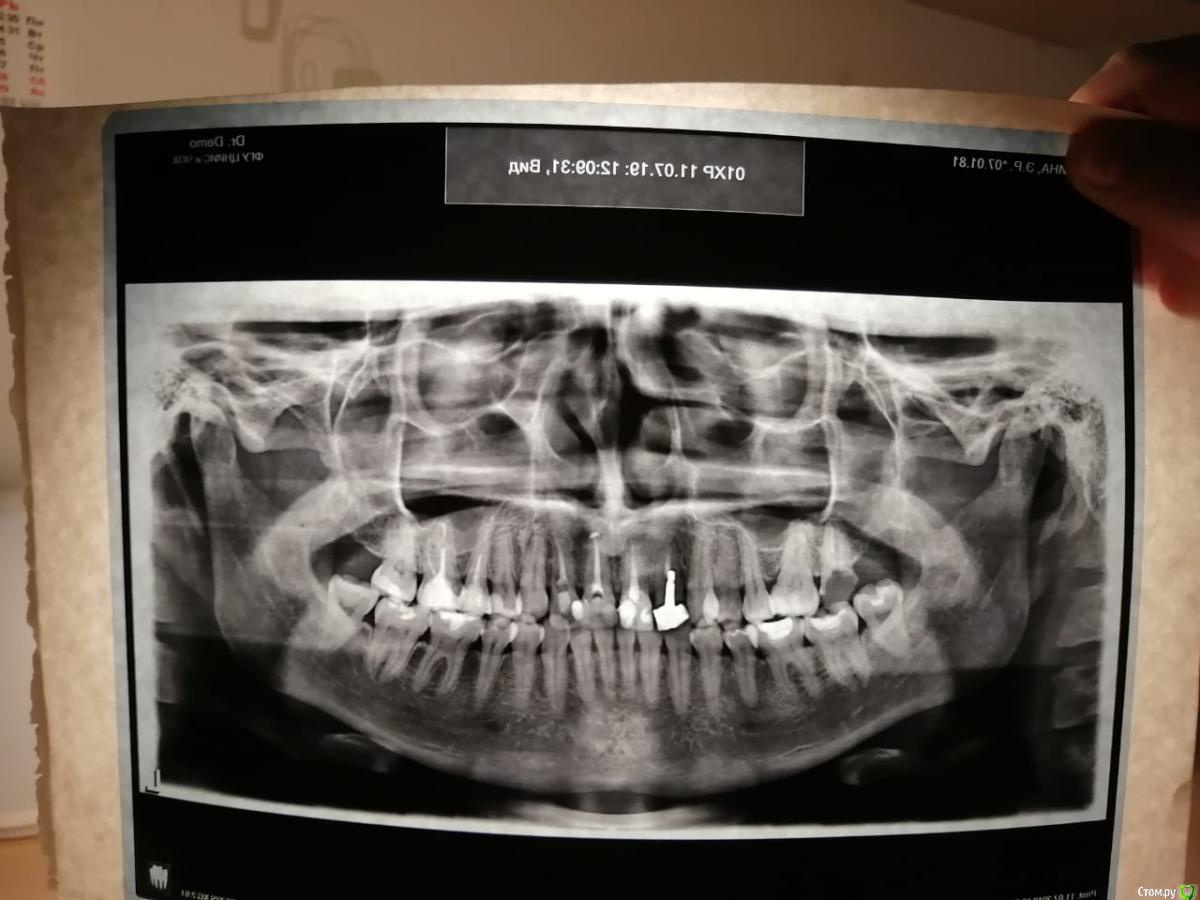

Эльза031008 Опубликовано 24 ноября, 2019 Поделиться Опубликовано 24 ноября, 2019 Добрый день уважаемые врачи . Помогите определиться с правильностью метода протезирования коронок на верхние передние зубы при мезиальном прикусе? Мне 38 лет, с рождения нижняя челюсть больше верхней, ордонтическое лечение не проходила , в верхнем ряду один зуб на штифте с 15 лет , сейчас встал вопрос о замене , штифт уже не заменить , при нескольких консультациях ортопеды не берутся ставить коронки или имплатант , или готовы сделать,но без гарантии, что конечно меня не устраивает. В итоге один ортопед предложил вариант протезирования после поднятия верхнего ряда , я согласилась на данный вариант. Сначала носила гибкую пластинку на ночь 2 месяца, а сейчас сделали пластмассовые временные коронки на весь верхний ряд , которые я должна носить не менее 6 месяцев , перед постановкой постоянных . Зубы не обтачивали, на них сверху прикрепили на весь ряд три готовые слитные коронки слева ,справа и спереди с подговленный гипс. модели , при этом верхний ряд вывели вперед за нижние путем утолщения коронок и на несколько мм выступ на нижние с помощью увеличения высоты . По прикусу мне не удобно в состоянии покоя, долго обтачивали чтобы подогнать коронки , но я чувствую что с прикусом все не так , жевательеые поверхности касаются только по внешнему краю внутри если проводить языком то есть пустоты , нижние передние садятся на верхние и я испытываю наибольшее давление именно на передние зубы, когда ем пища плохо пережевывается нижние передние зубы при этом проходяться по верхним с клацканьем. Когда уже все сделано я понимаю что методом ручной подгонки нельзя было делать... По ортодонтии несколько ортодонтов в том числе профессор Арсеньева сказала что поможет только операция , на операцию я не соглашусь , большие риски. Посоветуйте план возможного протезирования и где в Москве есть такие специалисты протезирующие с такой проблемой ?возможно ли предваоительное моделирование, чтобы более или менее подобрать коронки по прикусу и не вызвать дисфункцию суставов и было более менее комфортно? При этом текущие конструкции нужно снять? Ссылка на комментарий